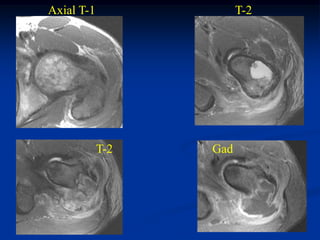

Axial T-2 MRI

Tumor seen thru cortical window